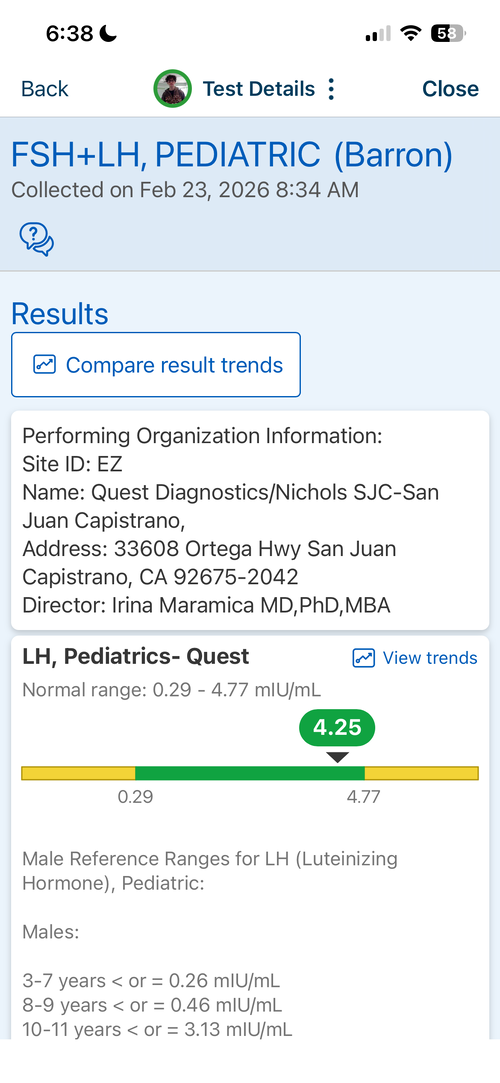

16.6 yr old male at 5'11.1" in height currently. Father is 6'1.5" and Mother is 5'8". I have images of my growth chart along with an X-Ray of my wrist attached. I also attached recent bloodwork tests of TESTOSTERONE, IGF-1 and Cortisol.